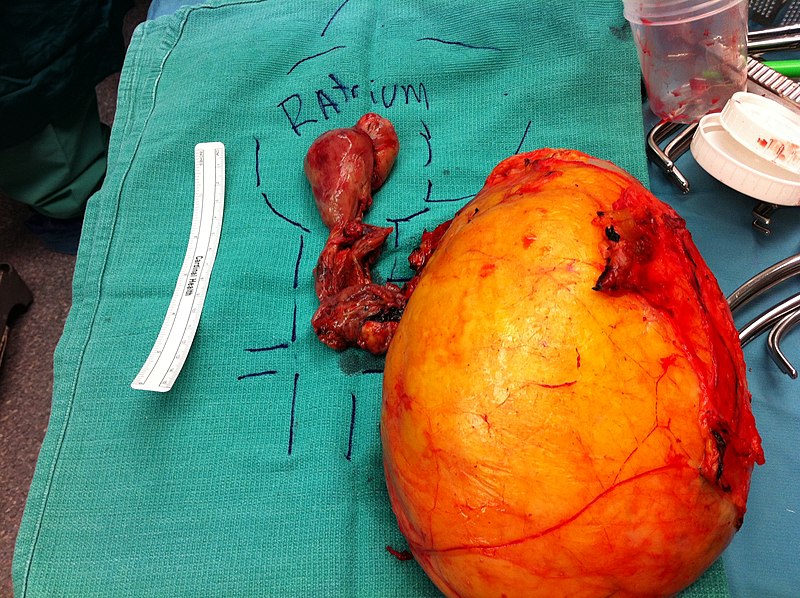

Renal Cell Carcinoma (RCC)

Renal cell carcinoma (RCC) is a malignant cancer cells are located in the lining of kidney tubules, which are incredibly tiny tubes. This condition is known as renal cell carcinoma.

Symptoms of renal cell carcinoma include:

- Hematuria (most common)

- Palpable mass

- Flank pain